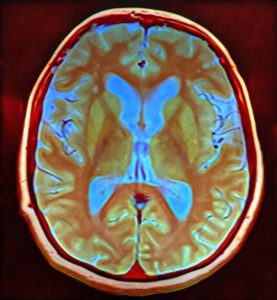

Mozog je pre človeka nesmierne dôležitým orgánom, zároveň sa k nemu viažu fascinujúce charakteristiky. Čítajte.

Ľudský mozog je jedným fascinujúcim orgánom, ktorý sa vedci snažia prebádať a zistiť o ňom čo najviac. Dalo by sa povedať, že jeho anatómia je už takmer dokonale preskúmaná, ale čo sa týka jeho fungovania, stále je čo objavovať.

Dôležité je hneď na úvod povedať, že cicavce a konkrétne my ľudia máme máme najväčší a najvyvinutejší mozog spomedzi všetkých na Zemi žijúcich organizmov. Ide o riadiace centrum, ktoré prijíma a spracováva celú škálu informácií z vonkajšieho a vnútorného prostredia a zároveň na ne generuje odpovede. Ide o orgán, kde už i najmenšia porucha môže mať katastrofálne až devastujúce účinky. Poďme si o ňom povedať viac.